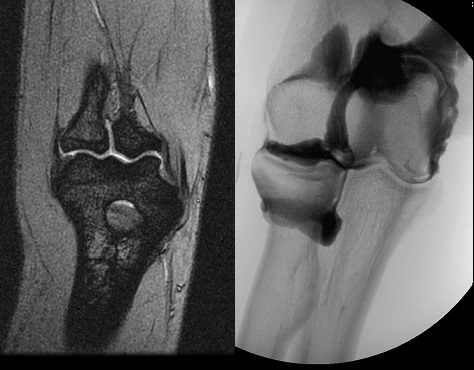

An 80 year old female presents to your office with a left ring finger deformity after a fall one week ago. She initially went to urgent care and xrays were unremarkable for a fracture (Figures 1 and 2). A photo of her left ring finger is shown in figure 3. On physical exam the left ring finger is in hyperextension at the PIP joint and flexion at the DIP joint. She able to flex her PIP joint with full motion. What is the best treatment option?